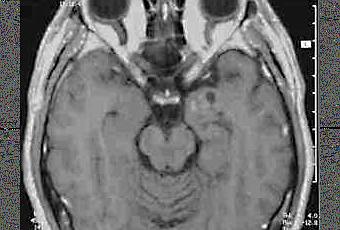

Tercera semana de la segunda vuelta, que se presentaba movidita por la densidad de la materia, pero que al final resultó ser bastante ligera. Supongo que es porque la Neurología me encanta y me parece súper lógica y intuitiva (ay, si tuviera un buen expediente y fuera una lumbreras encabezaría mi lista de opciones), o puede que porque sigo pensando que voy demasiado rápida en el estudio... no sé el por qué, pero a mediados de semana ya lo tenía todo estudiado, así que disfruté de dos días extra para repasarlo todo y hacer montones de preguntas.